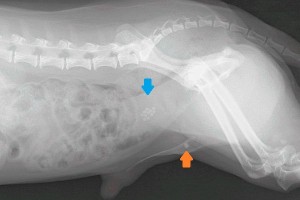

左 の写真は膀胱結石を患ったワンちゃんのX線写真です。青矢印が膀胱内に多数存在している結石です。橙矢印が尿道から出て陰茎骨手前まで流れて詰まってし まった結石です。右の写真は超音波検査で見えた膀胱内の結石です。超音波では液体は黒く描写されるので 、本来黒く見えるだけのはずの膀胱内に白いものが 見えています。

治療は、ストラバイト結石なら食餌療法で結石が溶ける可能性がありますが、外科手術で摘出する場合もあります。シュウ酸カルシウム結石なら食餌療法では溶 けないため、外科手術が選択となります。上のワンちゃんは尿道内の結石を膀胱内に押し戻してから手術で膀胱内の結石を取り出しました。